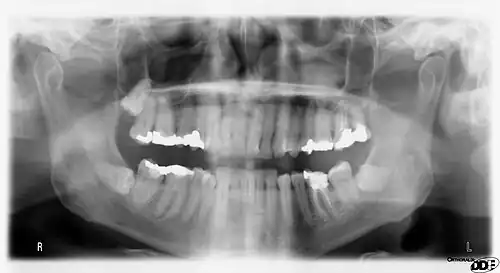

Minimally-displaced fracture in right mandibular. Arrow marks fracture, root canal on central incisor, teeth to the left of fracture do not touch